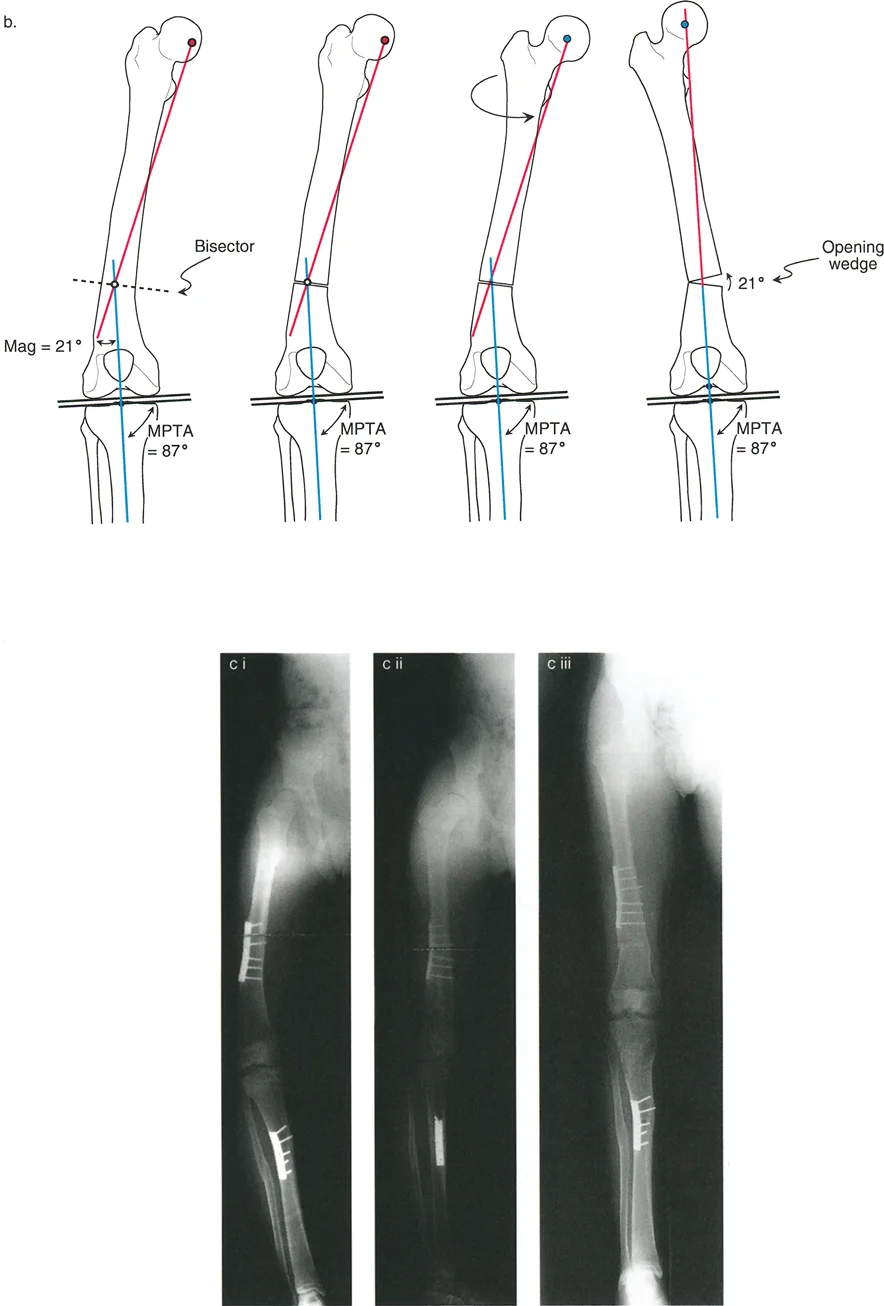

غالباً ما تتواجد هذه التشوهات معاً، مما يجعل الحالة أكثر تعقيداً. فمثلاً، قد يكون عظم الفخذ منحنيًا وفي نفس الوقت ملتفاً. هذا التداخل يخلق "تشوهاً ثلاثي الأبعاد" يتطلب فهماً عميقاً وكفاءة عالية لتصحيحه.

أهمية التصحيح ثلاثي الأبعاد

عندما يكون العظم مشوهاً في كل من الانحراف الزاوي والدوران، فإن أي محاولة لتصحيح أحد الجانبين دون الآخر قد تؤدي إلى نتائج عكسية أو حتى مضاعفات خطيرة. على سبيل المثال:

* إذا قمت بتصحيح الانحناء فقط وتجاهلت الدوران، فقد يظل المريض يعاني من مشكلة في المشي أو ألم في الركبة.

* إذا تم تصحيح الدوران بشكل خاطئ أو في مستوى غير صحيح، فقد يؤثر ذلك على عمل العضلات المحيطة، خاصة عضلات الفخذ الأمامية (الرباعية)، مما قد يؤدي إلى خلع صابونة الركبة أو تآكل غضروف الركبة (تلين الغضاريف).

* يمكن أن يؤدي التصحيح غير الدقيق أيضاً إلى شد غير طبيعي على الأعصاب والأوعية الدموية، مما قد يسبب تلفاً عصبياً مثل شلل العصب الشظوي، وهو ما يؤثر على القدرة على رفع القدم.

لهذا السبب، يركز الأستاذ الدكتور محمد هطيف على التخطيط الجراحي ثلاثي الأبعاد الذي يأخذ في الاعتبار كل زاوية وكل محور، لضمان تصحيح شامل ودقيق يحقق أفضل النتائج الوظيفية ويحافظ على سلامة المريض.

تحديد مستوى التشوه بدقة

إن تحديد المستوى الدقيق للتشوه الدوراني هو أحد أهم الخطوات في التخطيط الجراحي. على الرغم من أن الدوران هو تشوه زاوي في المستوى المستعرض، إلا أن موقعه على طول العظم (قريب من المفصل أو بعيد عنه) يؤثر بشكل كبير على كيفية تصحيحه وتأثيره على الأنسجة المحيطة.

- في حالات ما بعد الإصابة: يكون مستوى التشوه واضحاً عادة عند موقع الكسر الملتئم.

- في الحالات الخلقية أو التنموية: يتطلب تحديد مستوى التشوه استنتاجاً سريرياً دقيقاً يعتمد على تأثيره العميق على مسار العضلات والأوتار. يعتمد الدكتور هطيف على خبرته الواسعة في تقييم هذه الحالات لتحديد المستوى الأمثل لقطع العظم.

خيارات العلاج المتقدمة لتصحيح التشوهات الدورانية

عندما تكون تشوهات الدوران والانحراف الزاوي شديدة وتؤثر على وظيفة المريض أو تسبب ألماً مزمناً، يصبح التدخل الجراحي هو الحل الأكثر فعالية. تتطلب هذه الجراحات دقة متناهية وتخطيطاً متقدماً، وهو ما يبرع فيه الأستاذ الدكتور محمد هطيف